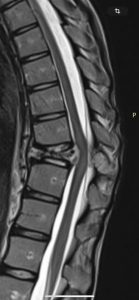

У дівчини, яка навчається в 10-му класі місцевого ліцею №1, діагностували пухлину грудного відділу хребта, повідомляє у Facebook Світлана Киричук.

Станом на зараз утворення вже почало стискати спинний мозок, що створює пряму загрозу здоров’ю дитини. Аделіна потребує термінової дороговартісної операції, яка дозволить їй позбутися болю та повернутися до нормального життя.